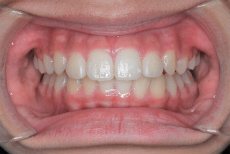

写真で確認できますように上あごの左右側12才臼歯がきちんと生えています。この噛み合わせに至るまで、本症例では固定式矯正装置での本格的矯正治療はせずにI期治療のみで終了しています。

せめてこの12才臼歯がしっかり生えてくるまでは治療の終了を急がずにじっくりと待つべし、ということです。